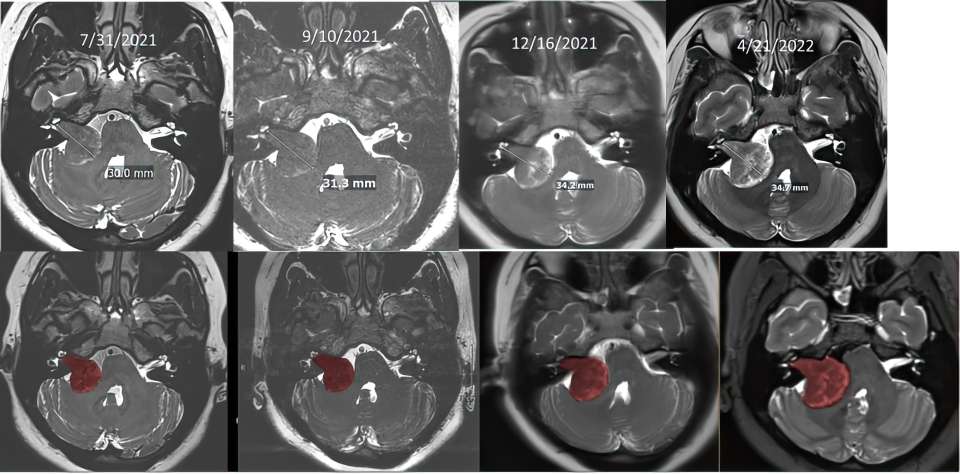

To monitor the growth of the tumor and the development of hydrocephalus, Sun underwent several scans throughout her pregnancy.

“We couldn’t use CT scans because they involve radiation, which can be harmful to the fetus,” explained Dr. Everson. “While an MRI is safe, the typical scan takes about an hour lying flat, which is difficult for patients to tolerate in late pregnancy. So, we worked closely with radiologist Dr. Noriko Salamon to devise a specific, shortened MRI protocol that gave us all the detail we needed to monitor tumor growth.”

brain scans

Throughout her pregnancy, Sun underwent multiple cans to closely monitor the tumor’s progression. Initially the size of a cherry, the tumor grew to the size of a golf ball.

The team observed subtle signs of tumor growth during Sun’s second and third trimesters and remained vigilant, closely monitoring her condition with frequent brain scans. This involved close collaboration with radiology, ENT specialists, and her OBGYN team, which included Carla Janzen, MD, PhD, an expert in maternal-fetal medicine and high-risk pregnancies, and obstetrician-gynecologist Brittany Davis, MD.

After the extensive surgery, Dr. Everson and his team were able to remove the now golf ball-sized tumor without any damage to the facial nerve. In the years since, the team has continued to monitor Sun to ensure everything stayed stable.